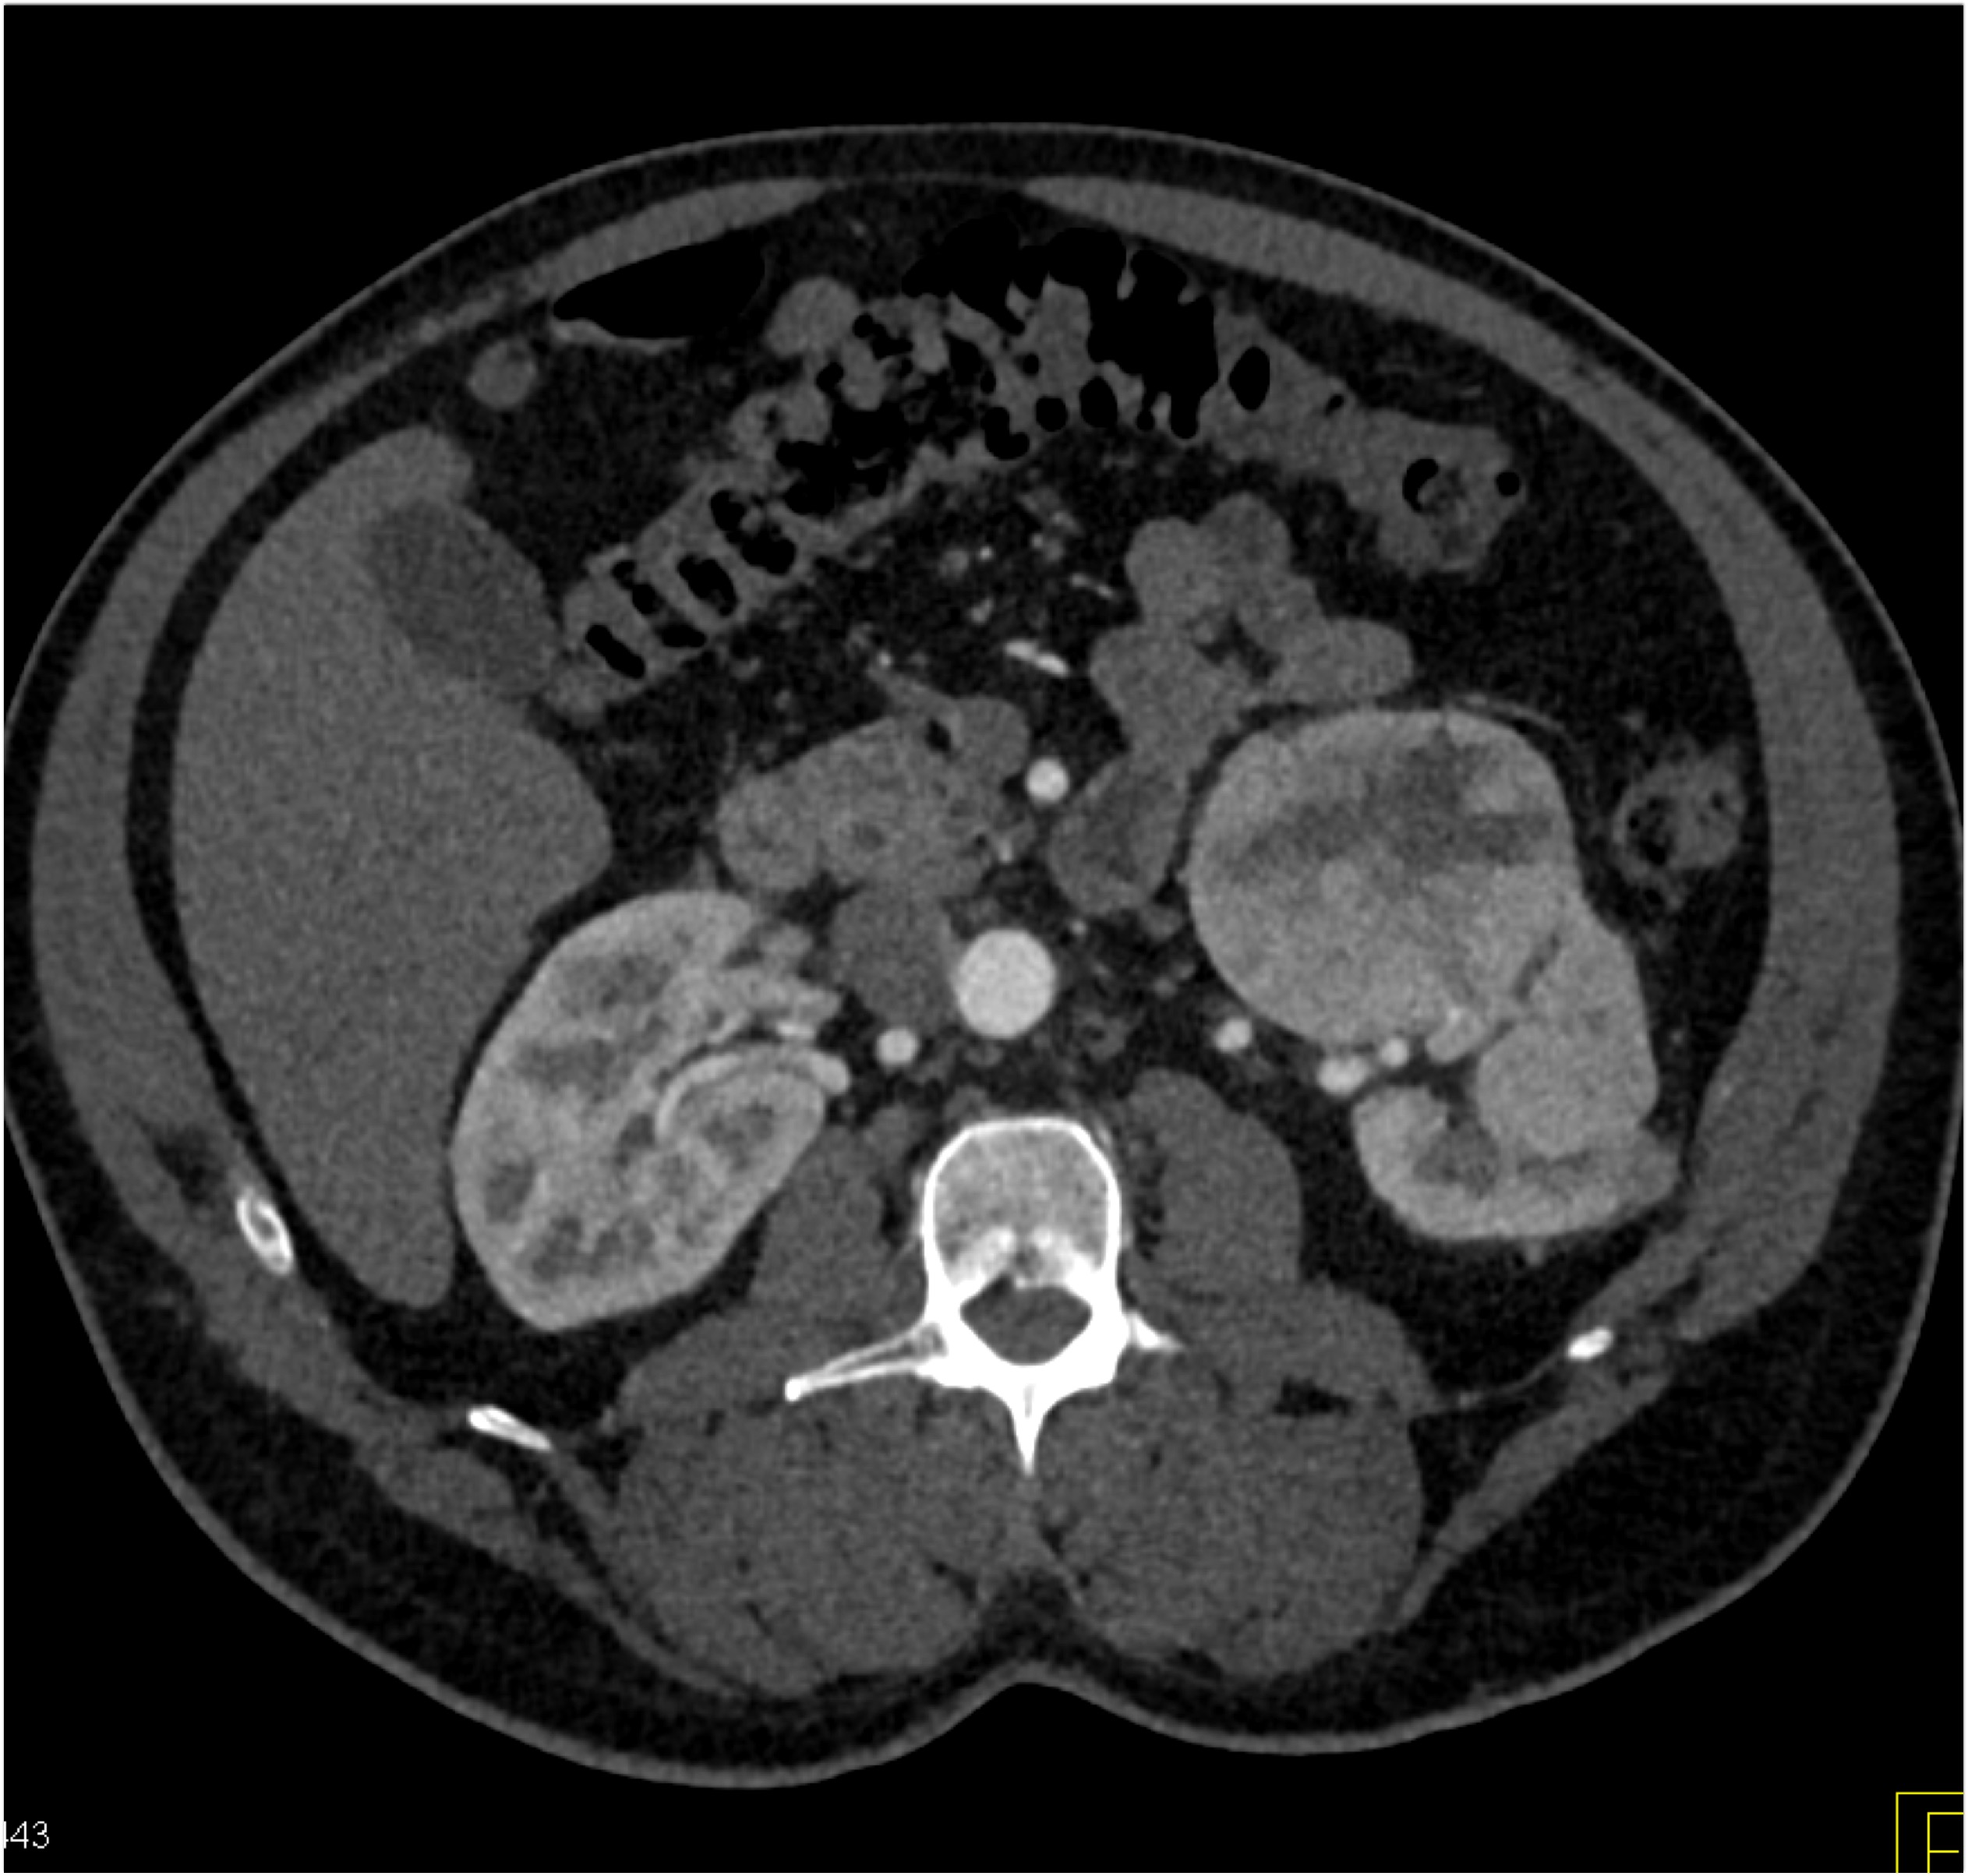

8) The most likely diagnosis for the dominant left renal mass is?

clear cell renal cell carcinoma

metastatic melanoma

papillary renal cell carcinoma

renal oncocytoma